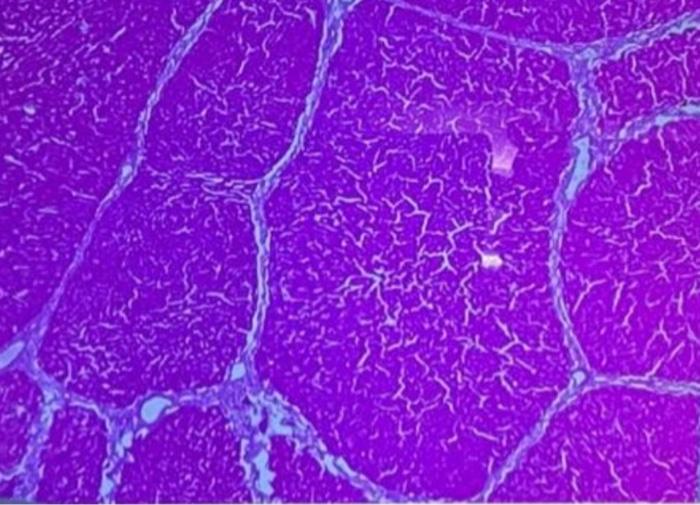

onto the image label:

hepatic veins, a cord, and connective tissue.

no explaniations just labeling